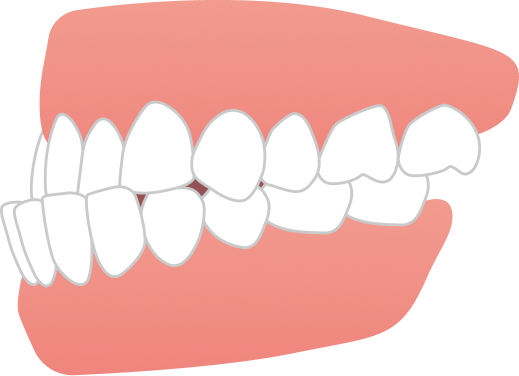

治療では、歯列全体のバランスと噛み合わせを考慮しながら計画を立て、抜歯を行うことなく、マウスピースのみで治療を進めました。治療期間は1年9ヶ月で、見た目の印象が大きく改善するとともに、機能的にも安定した噛み合わせが得られています。

自然な口元と噛みやすさの両立を実現できた症例です。

AFTER